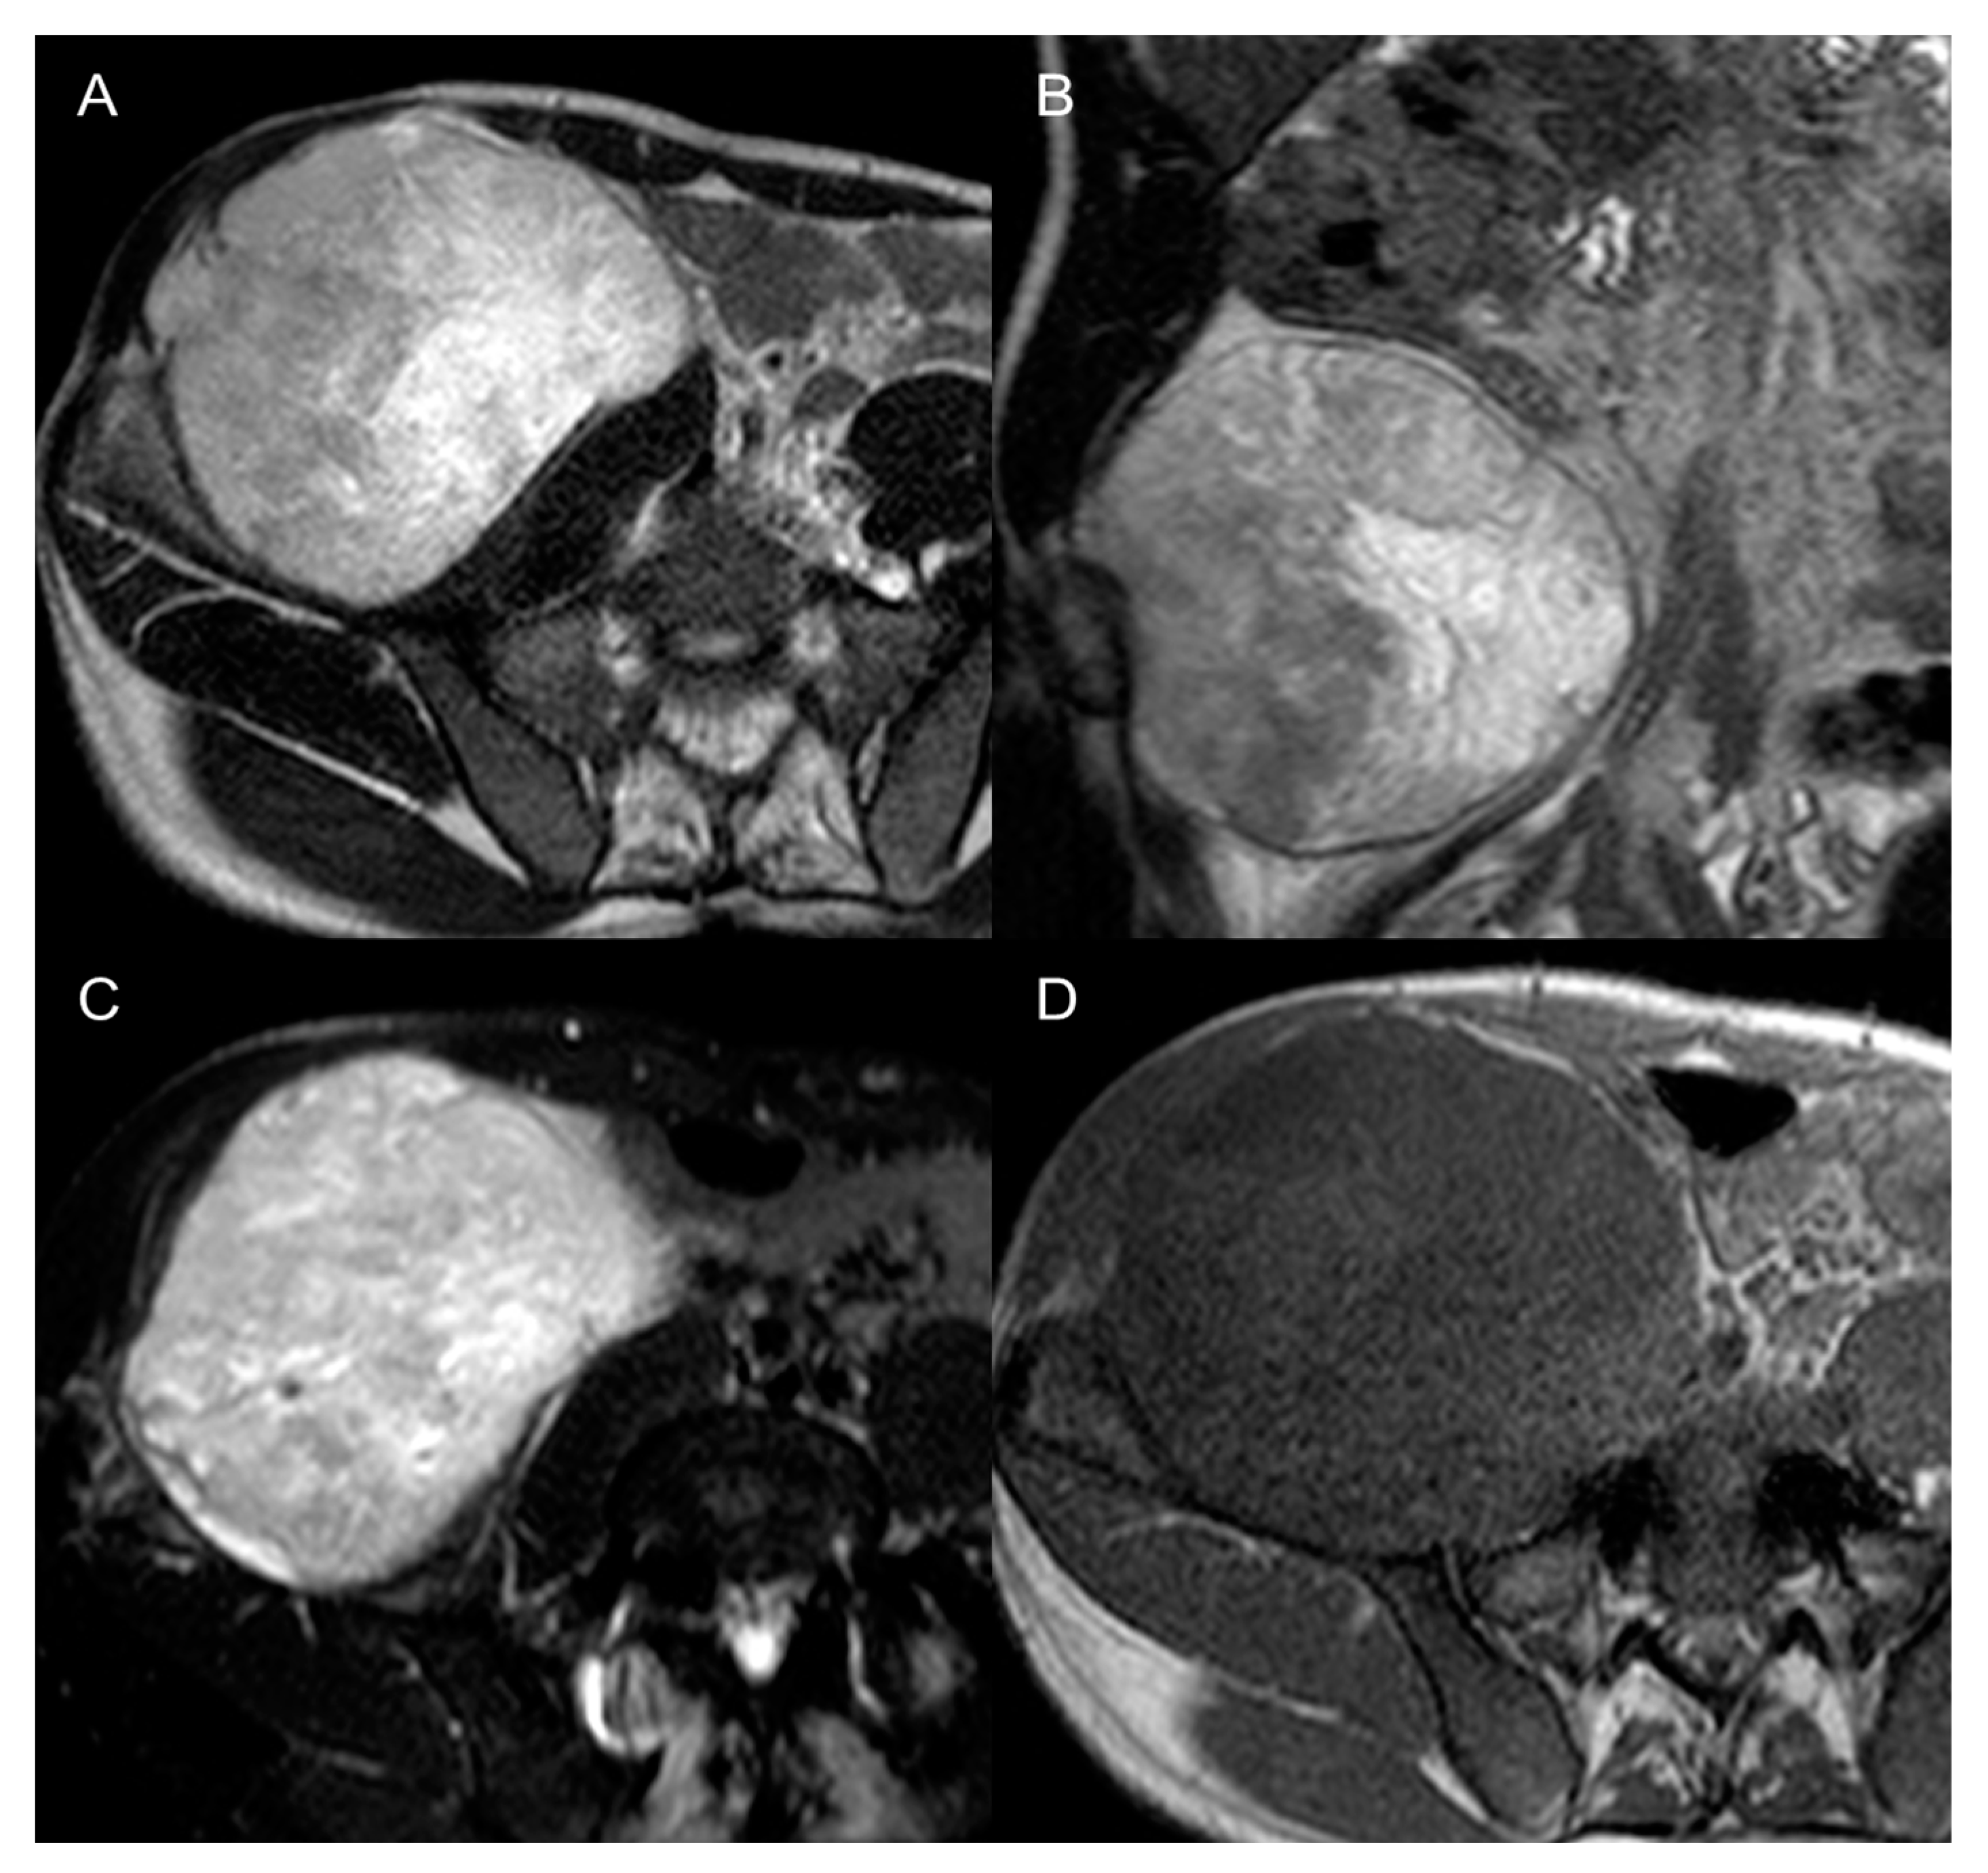

Contrast-enhanced MRI is the best modality to characterize a soft-tissue tumor, but also for local staging and prognosis. The diagnostic orientation can be facilitated on MRI by the identification of myxoid stroma (high fluid-like signal on T2, hypointense on T1, with contrast uptake), fatty content (Dixon [9] and Dual Echo), necrosis, hemorrhage, cystic degeneration, and fibrotic content. For instance, the presence of myxoid stroma can point towards myxoid round cells LPS, low-grade fibromyxoid chondrosarcoma, rhabdomyosarcoma (Figure 9), or small extraskeletal myxoid chondrosarcoma [9]. Undifferentiated sarcoma, instead, can present as massively hemorrhagic tumors, therefore being similar to a large hematoma, that does not have an explanation, nor a rapid appearance or resolution [6,9].

Figure 9.

Pleomorphic rhabdomyosarcomas in a 37-year-old man. Axial (A) and coronal (B) T2-weighted MR images, axial SPAIR (C), and axial T1 GRE (D) images show a 12 cm large heterogenous mass in the right retroperitoneum. The lesion was histologically confirmed at biopsy.